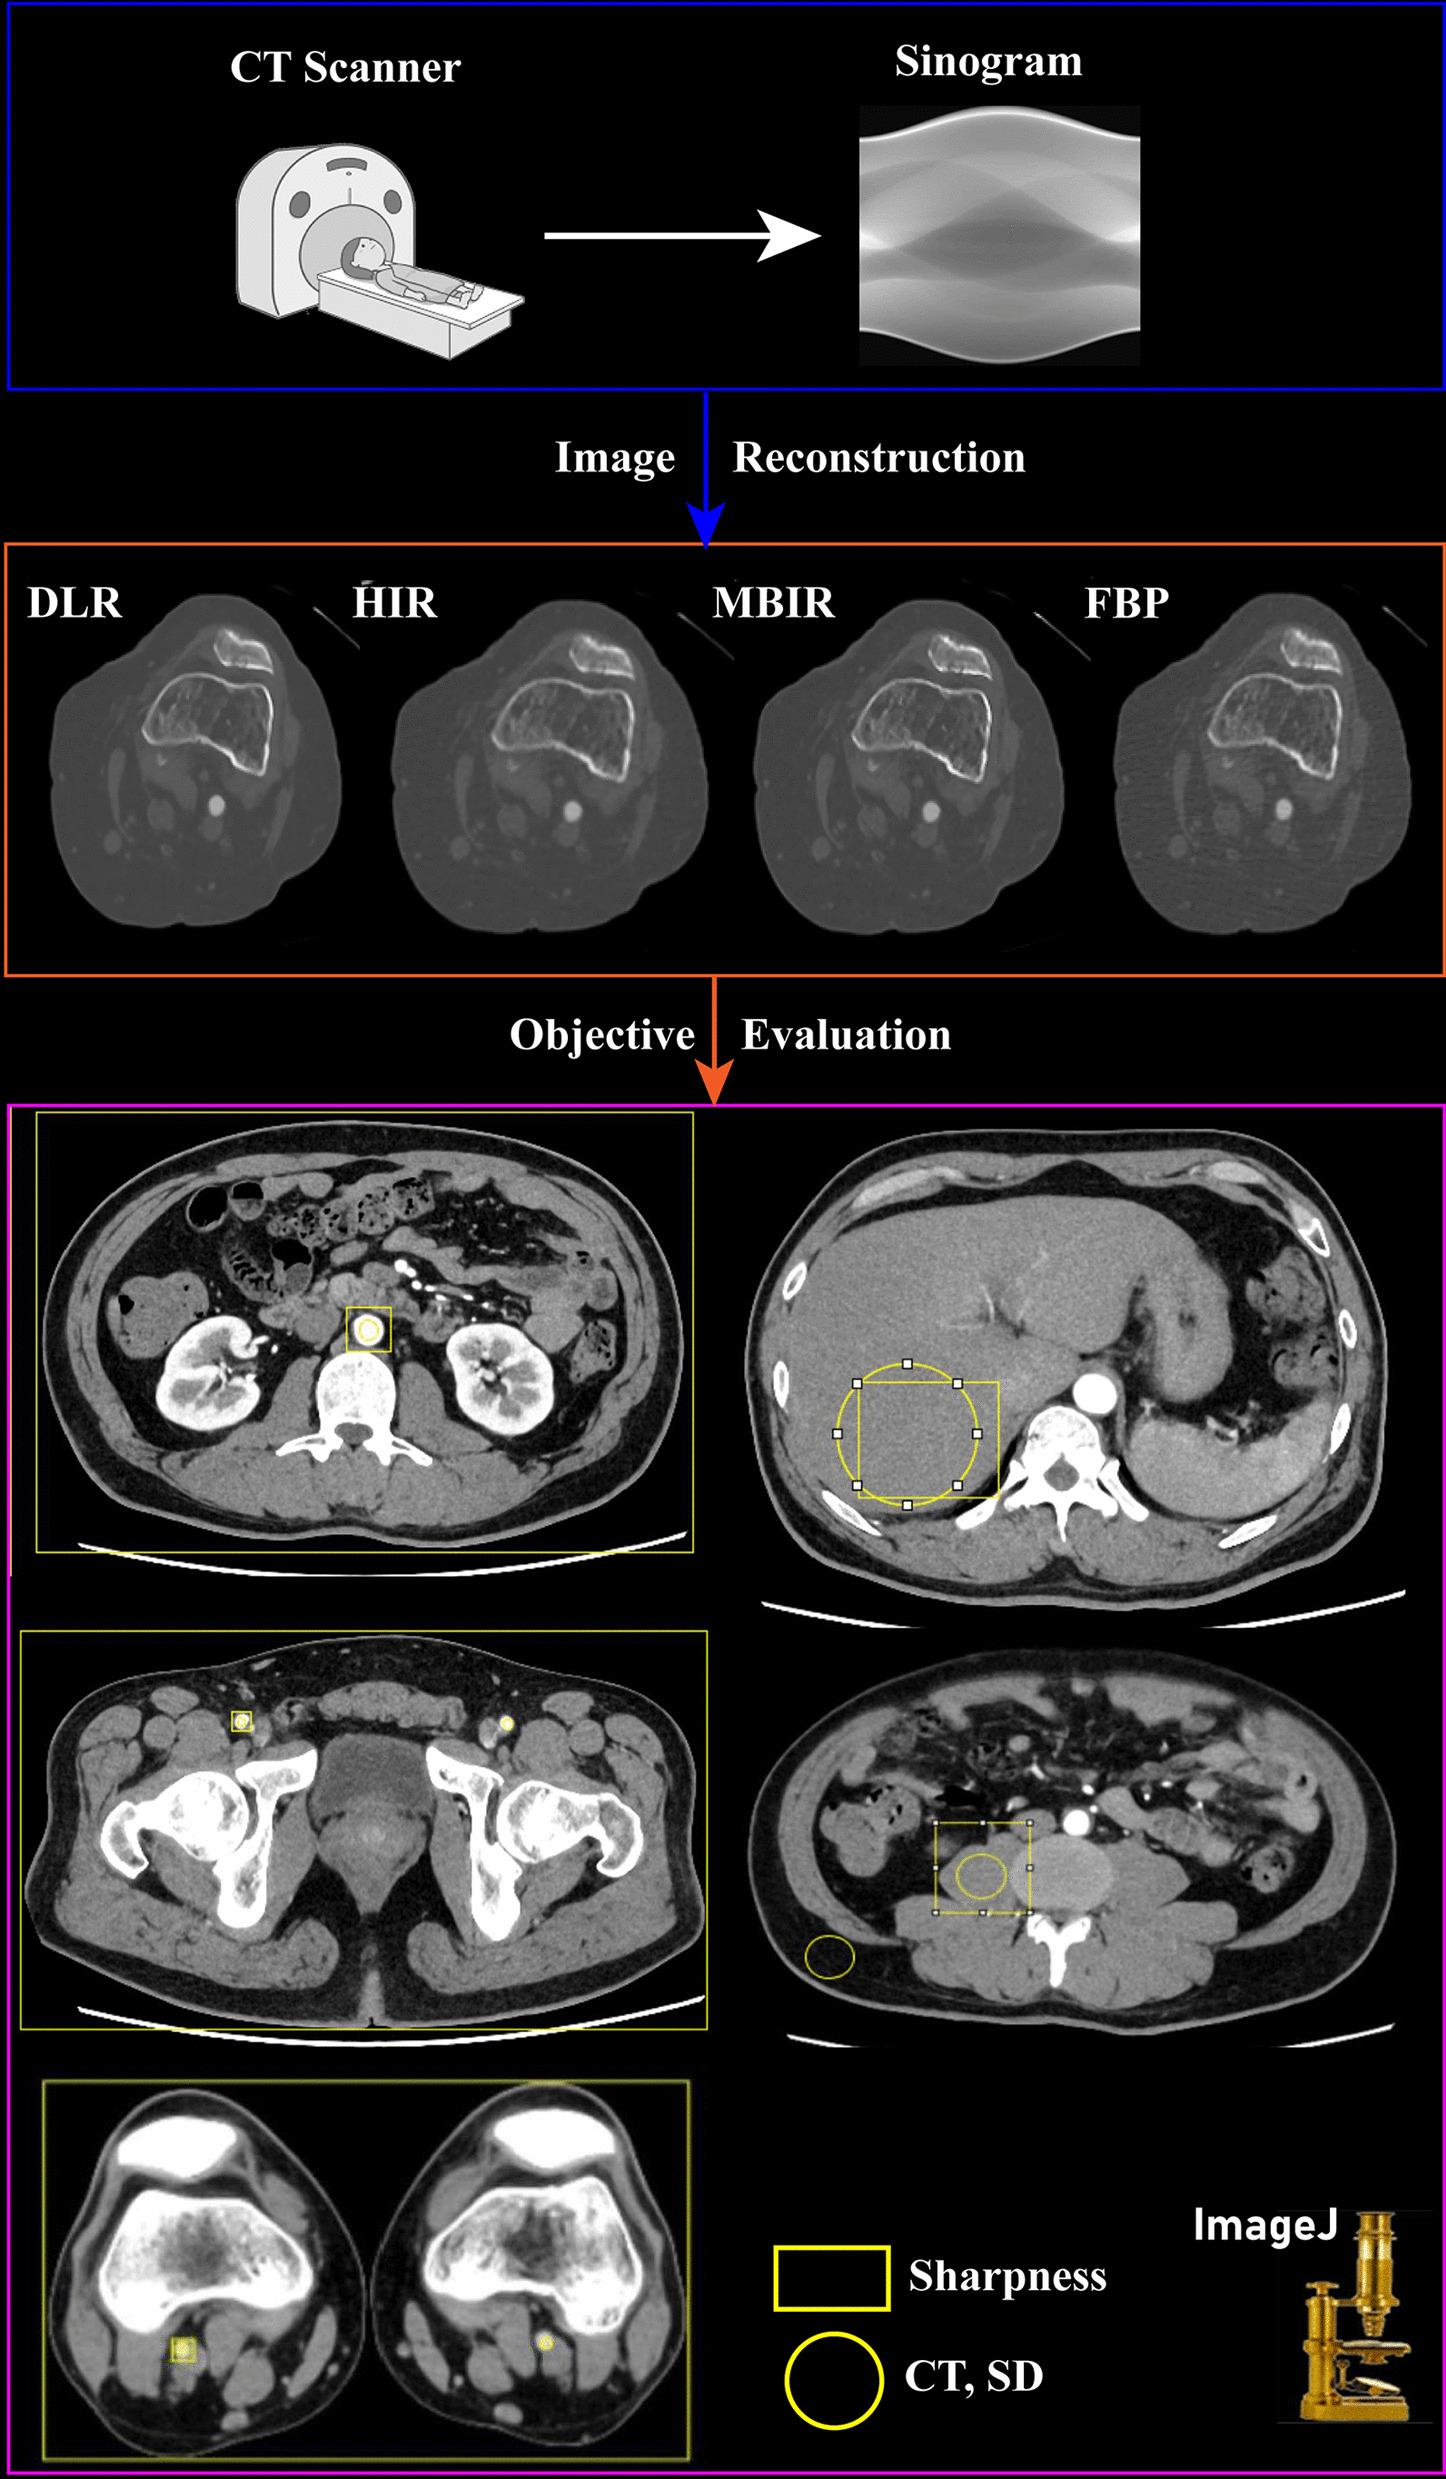

To evaluate the image quality of lower extremity computed tomography angiography (CTA) with deep learning-based reconstruction (DLR) compared to model-based iterative reconstruction (MBIR), hybrid-iterative reconstruction (HIR), and filtered back projection (FBP).

Fifty patients (38 males, average age 59.8 ± 19.2 years) who underwent lower extremity CTA between January and May 2021 were included. Images were reconstructed with DLR, MBIR, HIR, and FBP. The standard deviation (SD), contrast-to-noise ratio (CNR), signal-to-noise ratio (SNR), noise power spectrum (NPS) curves, and the blur effect, were calculated. The subjective image quality was independently evaluated by two radiologists. The diagnostic accuracy of DLR, MBIR, HIR, and FBP reconstruction algorithms was calculated.

The CNR and SNR were significantly higher in DLR images than in the other three reconstruction algorithms, and the SD was significantly lower in DLR images of the soft tissues. The noise magnitude was the lowest with DLR. The NPS average spatial frequency (f) values were higher using DLR than HIR. For blur effect evaluation, DLR and FBP were similar for soft tissues and the popliteal artery, which was better than HIR and worse than MBIR. In the aorta and femoral arteries, the blur effect of DLR was worse than MBIR and FBP and better than HIR. The subjective image quality score of DLR was the highest. The sensitivity and specificity of the lower extremity CTA with DLR were the highest in the four reconstruction algorithms with 98.4% and 97.2%, respectively.

Compared to the other three reconstruction algorithms, DLR showed better objective and subjective image quality. The blur effect of the DLR was better than that of the HIR. The diagnostic accuracy of lower extremity CTA with DLR was the best among the four reconstruction algorithms.